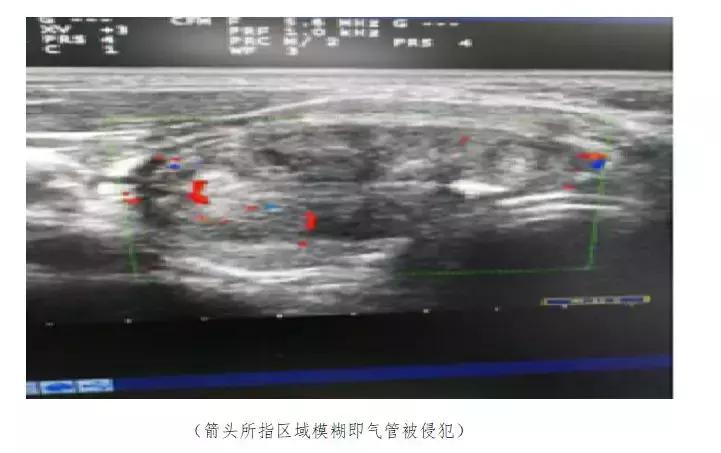

医生为吴大爷做了超声检查,检查结果显示:甲状腺左侧结节明显增大,内回声不均,可见斑点状钙化,医生建议他到专科医院做进一步的专业诊断。吴大爷这才来到了成都中科甲状腺医院,经超声介入科带头人李桂英主任检查,确诊为甲状腺乳头状癌,且已经侵犯气管,并伴颈部多发淋巴结转移。